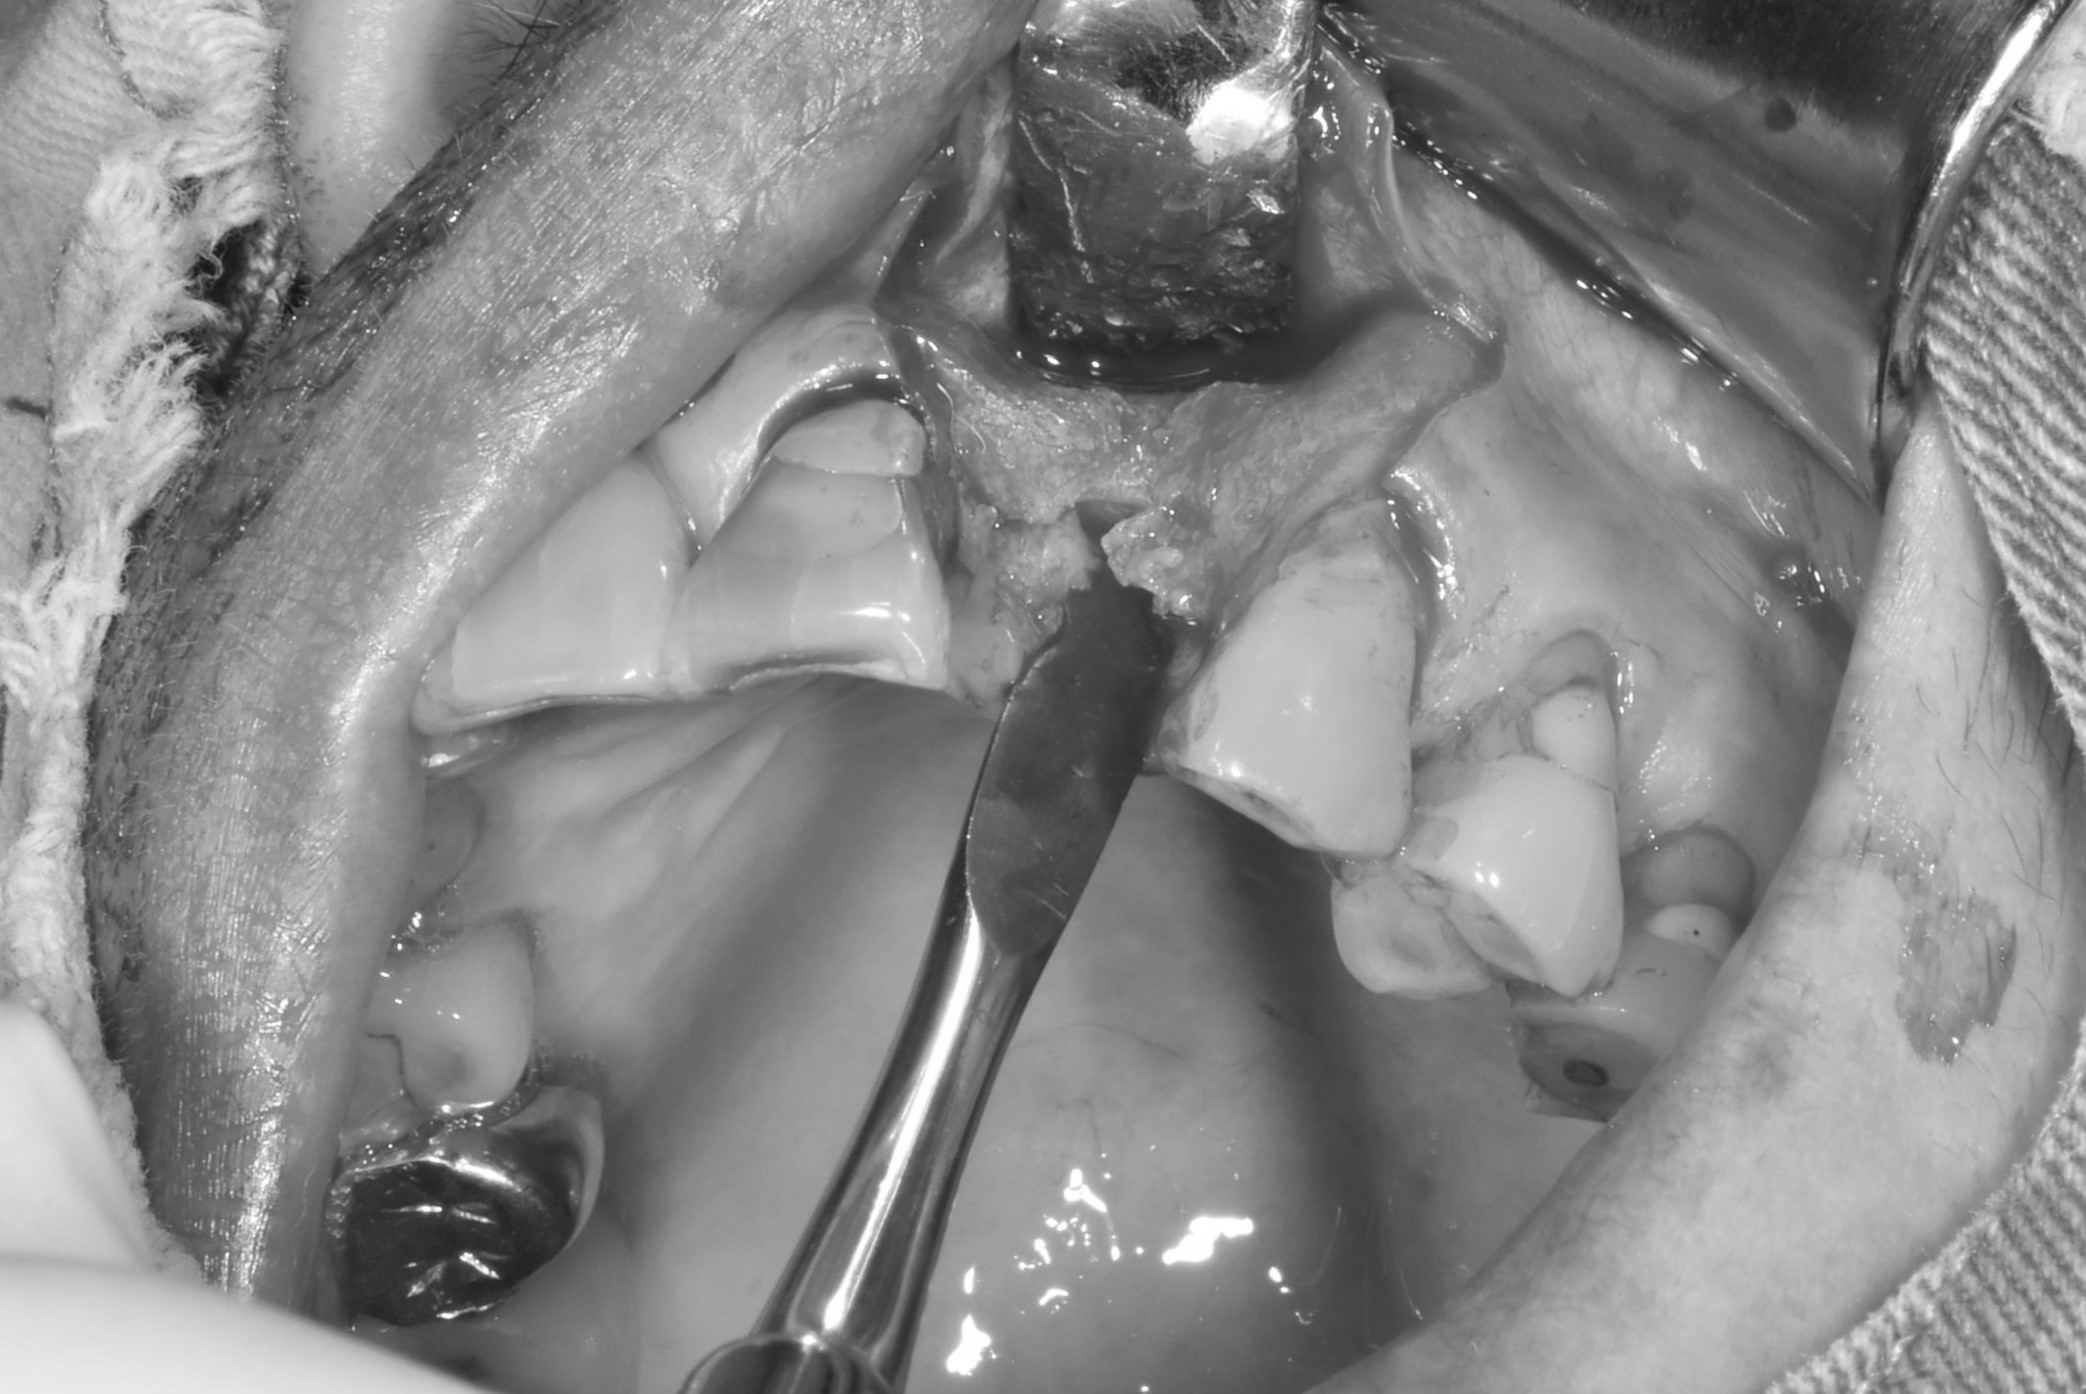

案例二

骨頭明顯凹陷

翻瓣補骨的區域

補入所需的骨粉